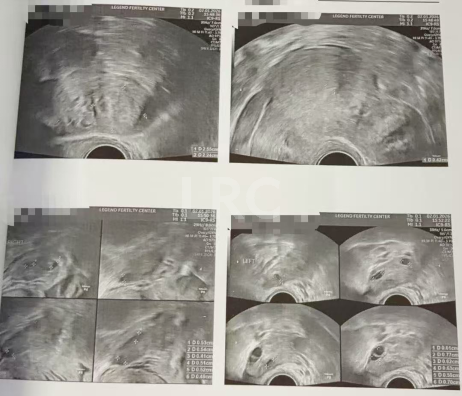

促排第十天

阴超检查:

- 右侧卵泡 4 颗 (18,18,16,13mm)

- 左侧卵泡 6 颗 (22,21,20,20,17,13mm)

子宫内膜厚度:10.2 mm